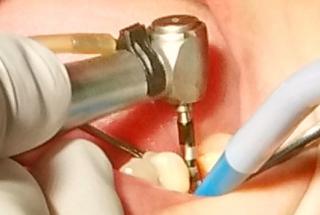

Clinical cases

MPI closely monitors clinical cases in the market to ensure their correct functioning and successful outcome.